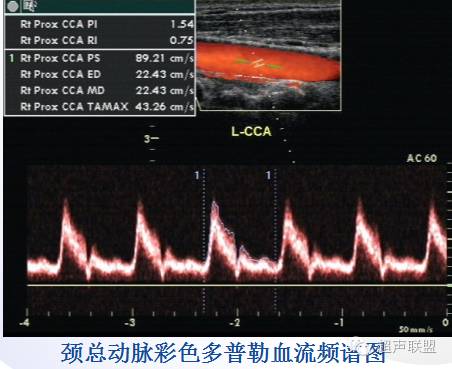

颈部动脉 | 内径cm | Vs (m/s) | 血流阻力RI | 颈部位置与走行 | 颈部分支 | 颞浅动脉拍击试验 |

颈总动脉CCA | 0.6—0.7 | 0.91±0.2 | 0.7±0.005 | 气管旁 | ICA、ECA | 频谱无明显改变 |

4、 PW记录CCA无病变处血流频谱并测量PSV:取样点在分叉处以下4cm;SV置于血管中心轴线上;Doppler角度300-600。